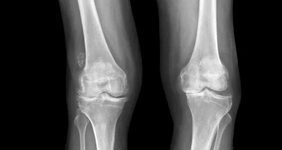

무릎 관절염이 의심될 경우 병원에서 영상 검사를 통해 확진할 수 있다.

✔ 엑스레이 (X-ray) – 연골 손상, 관절 간격 감소, 뼈 돌출 확인

🚗 TIP: 초기에는 X-ray 검사만으로도 진단이 가능하지만, 정밀 검사가 필요하면 MRI를 추가로 시행한다.